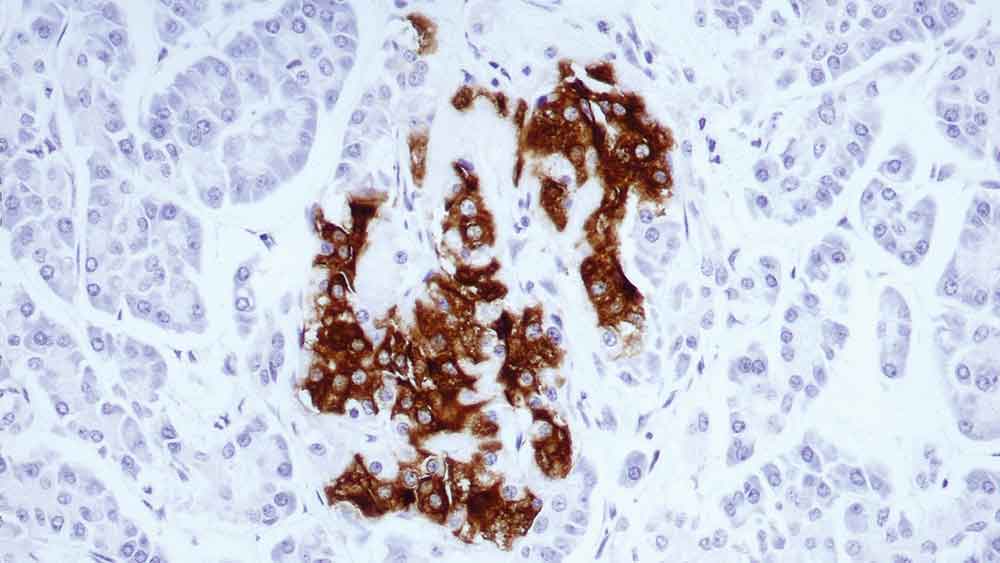

Human pancreas: immunohistochemical staining for insulin-containing cells. Note intense cytoplasmic staining. Insulin: clone 2D11-H5

L'insuline est une hormone sécrétée par les cellules bêta des îlots de Langerhans du pancréas. Elle favorise le stockage du glycogène, la formation de triglycérides et la synthèse des protéines et des acides nucléiques.

Des études immunocytochimiques ont révélé la présence d'insuline dans le cytoplasme de certaines tumeurs des îlots.

Cependant, dans certains cas, les granules insuline-positifs sont épars et forment une bordure contre la membrane cellulaire.